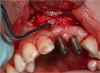

Fig. 5 and Fig. 6 The implant being placed virtually relative to available bone, soft tissue, and final restoration. In this case a screw-retained restoration was the goal and a buccal bone graft was planned prior to surgery. Because the surgery was planned and the area requiring grafting was known, a conservative flap sparing the papilla could be done.

Figure 5

Figure 6